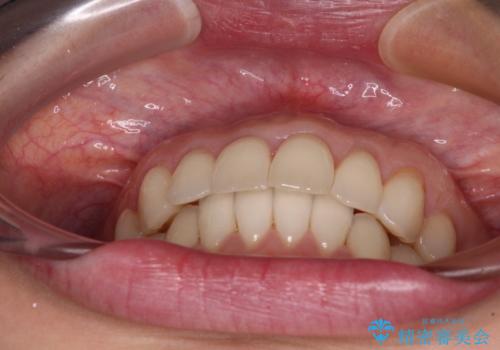

- 上下の前歯のデコボコを気にして来院された患者様です。

妊娠中であり、途中通院が難しくなる可能性があることから、インビザラインによる矯正治療を行うこととしました。

上下顎歯列全体の後方移動とIPR(歯と歯の間を削る)によってデコボコが解消するように設計しました。